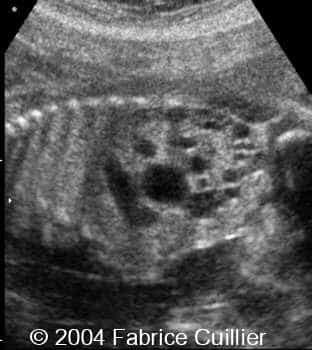

Multicystic kidney disease, unilateral, in a twin

This is a case of unilateral multicystic kidney disease in a twin with no other anomalies.